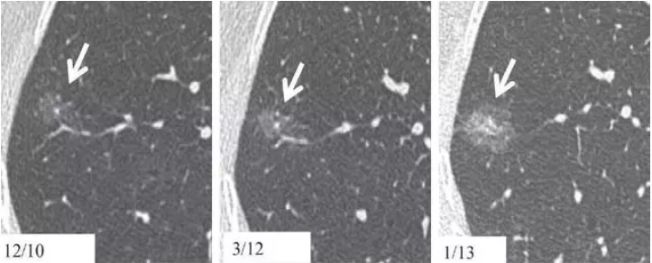

在中国人的印象里 心和肺一直是“形影不离”的 海尔兄弟 成语里有 撕心裂肺 狼心狗肺 没心没肺 …… 医学术语里有 心肺功能 心肺复苏 心肺康复 …… 尤其是当肺部查出“小阴影” 心更是脱不了关系 每天都惴惴不安 今天肿医君就来带大家看看 这让人烦恼的 肺部结节 Part.1: 肺部结节 真实病例: 张阿姨今年48岁,单位体检结果显示,肺上有一个0.8cm的小结节。张阿姨听说肺结节会变成肺癌,她担心极了,让儿子帮忙上网查询,向其他人咨询,可她得到的建议多种多样,让刘阿姨无所适从。 慢慢长大会不会变成肺癌啊 肺癌是世界上发病率及死亡率最高的恶性肿瘤,也是我国发病率和死亡率最高的疾病。目前约 75% 的肺癌患者在诊断时已属晚期,5年生存率仅为 15.6%。提高肺癌生存率的唯一途径是端口前移,早发现、早诊断和早治疗。 美国《化学文摘》2018全球癌症统计报告显示 肺癌(蓝色)高居发病率和死亡率之首 全球发病率11.6% 全球死亡率18.4% 湖南省肿瘤医院胸外一科 主任医师 陈跃军 很多患者忧心忡忡,不知道是否该进行进一步检查。如果对体检报告中的一些疾病迹象置若罔闻,等“小结节”长大变成了“肿块”,往往已错过最佳手术时机。那么我们应该怎么正确对待肺部结节呢? Part.2: 结节的分类 知识点 肺部结节(solitary pulmonary nodule,简称SPN)是肺实质完全包围的单发小病灶,类圆形或不规则形状,通常边界清晰,由肺实质包裹,不累及肺门和胸腔纵隔胸膜,不引发肺炎、肺不张或胸腔积液的组织。 肺结节分类如下 按大小: 肺结节中,直径1cm以内的称为小结节,直径0.5cm以内为微结节。局部病灶直径>3cm者称为肺肿块,也有医院将其报告为肺肿物或肺占位。 肺部结节尺寸越大,肺癌的可能性相对较大。 按数量: 肺结节可以是孤立性或多发性,孤立性肺结节即单个病灶,多无明显症状,属于边界清楚、密度增高且周围被含气肺组织包绕的软组织影。2个及以上病灶称为多发性肺结节。 肺结节的个数与肺癌可能性没有相关性 按密度: 根据病灶密度不同,肺结节还可分为实性肺结节和亚实性(非实性)肺结节,后者包括纯磨玻璃样结节。实性肺结节是肺内局限的密度增高影,病变密度相对较高,掩盖其中走行的肺细小支气管影和血管影(肺纹理);纯磨玻璃结节指CT显示的肺内密度稍增高影,通过病灶仍然能看到肺纹理影,就像透过磨玻璃观察到相对模糊的影像一样。 磨玻璃样结节尤其是持续存在的磨玻璃样结节,一般是肿瘤性病变 湖南省肿瘤医院胸外一科 主任医师 陈跃军 发现肺结节之后,不用过分紧张,但也不能掉以轻心,大部分肺结节都是良性的,只有少数肺结节是恶性的。 Part.3: 区分结节性质 结节良性的三大表现 1、 结构清晰,边缘平滑。内含脂肪和钙化的实性结节(箭头),符合错构瘤表现。建议进一步 CT 随访。 源自美国Fleischner 学会2017 年公布案例图(下同) 2、 有明显钙化痕迹。CT 图像显示边界清楚的中心钙化(a)或层状钙化(b)结节,均为典型的肉芽肿表现。建议进一步 CT 随访。 3、没有变大的趋势,甚至逐渐消失。(a)左肺上叶层厚 1 mm 的 CT 横断面图像,显示一个模糊的 10 mm 大小磨玻璃样结节(箭头)。(b)4 个月后的 CT 随访图像,显示未经治疗的病变在随访间期消失,符合良性病因,如局灶性感染。 结节恶性的三大表现 1、 毛刺状结节 左肺上叶层厚 1 mm 的 CT 横断面图像,显示一个可疑的实性毛刺状结节(箭头)。手术证实为浸润性腺癌。 2、 磨玻璃区域逐渐长大的结节 (a)右肺中部层厚 1 mm 的 CT 横断面图像,显示一个 10 mm 大小的纯磨玻璃样结节(箭头)。(b)同一位置 15 个月后的 CT 随访图像,显示病变的不透明度只有很小增加。(c)取得 b 图 10 个月后,同一位置的 CT 图像,显示结节已发展成较大的实性结节。手术切除证实为 1A 期浸润性鳞屑样为主的腺癌 3、实性结节逐渐变大的结节 (a)右肺下叶上段层厚 1 mm 的 CT 横断面图像,显示一个高度可疑(较大、磨玻璃样外观和实性形态)的部分实性结节(箭头)。(b)3 个月后的 CT 随访图像显示,实性成分的大小逐渐增加。手术显示为浸润性腺癌。 除了上述影像资料,咨询者的生活方式也是判断依据。 肺癌的高危人群 (1)年龄在55岁以上; (2)年数乘以每天吸烟的支数>400支*年的吸烟患者,其中也包括曾经吸烟,但戒烟时间不足15年者;被动吸烟者; (3)有职业暴露史(石棉、铍、铀、氡等接触者); (4)有恶性肿瘤病史或肺癌家族史; (5)有慢性阻塞性肺疾病(COPD)或弥漫性肺纤维化病史。 Part.4: 发现结节怎么做? 1、肺部小结节并不等于肺癌,并且大部分是良性的,有的通过保守治疗如抗炎或抗痨治疗,甚至不做任何治疗观察后消失。因为人体有自身免疫力的,只要营养好,一般的炎性病变可自行吸收。 2、当医生判断结节恶性可能性较小时,还是建议患者要定期检查胸部CT。5毫米以下的微结节每年复查一次,5至10毫米的小结节每三个月复查一次,随访三至五年。 CT在肺内病变中的诊断优势非常明显,CT通过显示组织横断面及三维结构图像进行诊查,有效避免了肺与心脏、纵隔、横膈等组织的重叠,能发现肺尖、脊柱旁、靠近胸膜、心脏后方等部位胸片难以发现的病灶。另外,低剂量CT筛查所产生的射线剂量很低,对人体的影响极低。 3、当医生判断为恶性可能性较大时,应早期进行手术(胸腔镜)治疗。国内外多个研究结果显示,经过手术治疗的I期患者的10年生存率达到了90%以上。 目前微创胸腔镜手术是治疗肺部小结节、早期肺癌的主要方法。胸腔镜手术应用广泛,只需一个1cm胸腔镜观察孔和一个2-3cm操作孔,行肺叶或肺段切除术,疗效明确,创伤非常小,疼痛轻,术后恢复快,不需要做任何的化疗和放疗。 在我们临床工作中对上千例磨玻璃结节、微小结节患者的长期临床观察研究结果显示,90%以上患者的结节没有发生变化,10%的患者在随访过程中发现结节长大或实质成分增加等改变,及时手术,但没有一例出现复发转移,所以只要找对了专家,定期随访,并不会耽误治疗。 最危险的情况其实是病人发现肺部结节去看医生,医生考虑肺部小结节可暂时不处理,建议定期复查,而病人把不手术、不服药误认为没病,一直拖到出现症状后再去就诊,耽误了病情。